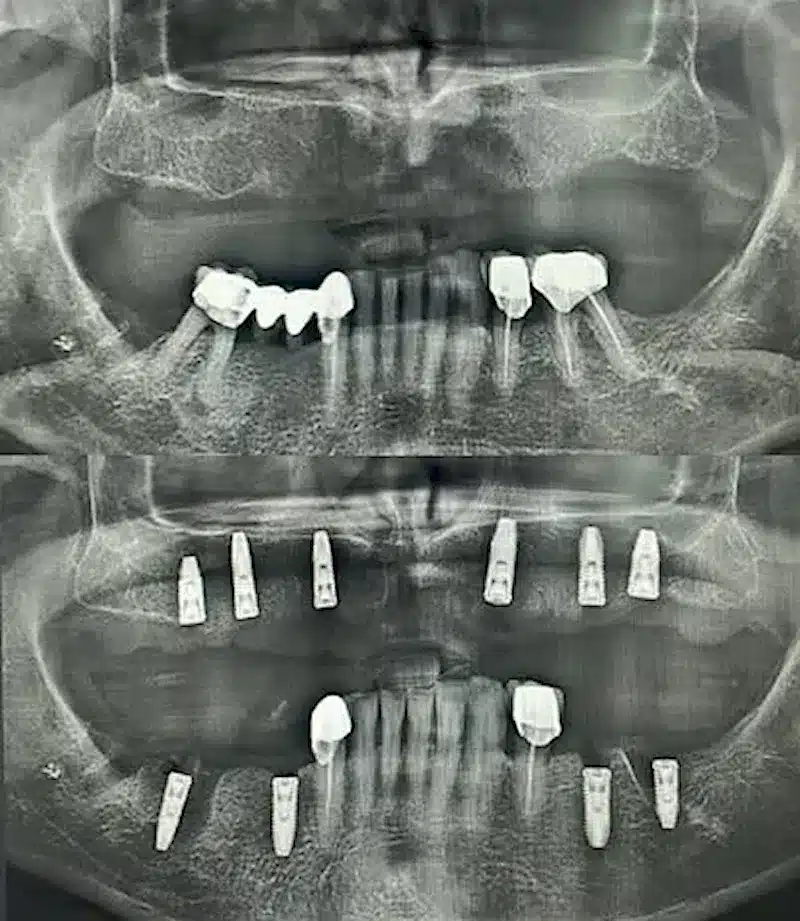

Dr. Seden Aksu is a specialist in modern implantology and surgical dentistry with extensive experience in the management of complex clinical cases. In her practice, she applies comprehensive surgical planning, minimally invasive techniques, and advanced regenerative technologies aimed at restoring both the function of the dentoalveolar system and the aesthetics of the smile. Dr. Aksu has significant experience in performing implant procedures, bone augmentation, and periodontal surgery, including the treatment of patients with severe bone loss. The primary goal of her work is to achieve stable, long-term outcomes in implant rehabilitation and the restoration of oral tissue health.